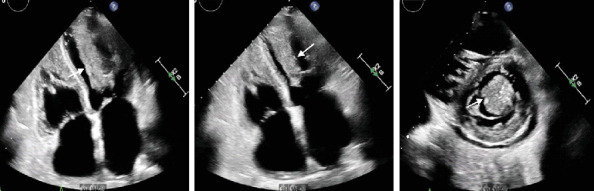

Background: Cardiac metastases, though more common than primary cardiac tumors, remain under-recognized due to their often subtle clinical presentation. These tumors can lead to life-threatening complications, and their diagnosis is typically delayed. Objective: This paper is aimed at reviewing two distinct cases of metastatic cardiac tumors, shedding light on diagnostic challenges, clinical presentations, and management approaches. Methods: We present two cases of patients with metastatic melanoma and undifferentiated malignant spindle cell neoplasm, respectively. Diagnostic imaging, including echocardiography and PET scans, was used to identify the cardiac masses, and biopsy results provided histopathological confirmation. Treatment plans involved systemic immunotherapy, chemotherapy, and surgical resection. Results: In both cases, cardiac metastases were detected through advanced imaging, despite the patients presenting with nonspecific symptoms like abdominal pain and shortness of breath. The metastatic tumor in one patient responded to immunotherapy before surgical excision, while the other patient, in advanced stages, opted for supportive care. Conclusion: Cardiac metastasis should be considered in cancer patients who present with unexplained cardiac symptoms. A multidisciplinary approach, including imaging and biopsy, is crucial for accurate diagnosis. Despite aggressive treatment, the prognosis remains poor, emphasizing the need for early detection and better therapeutic strategies.

Abstract Image